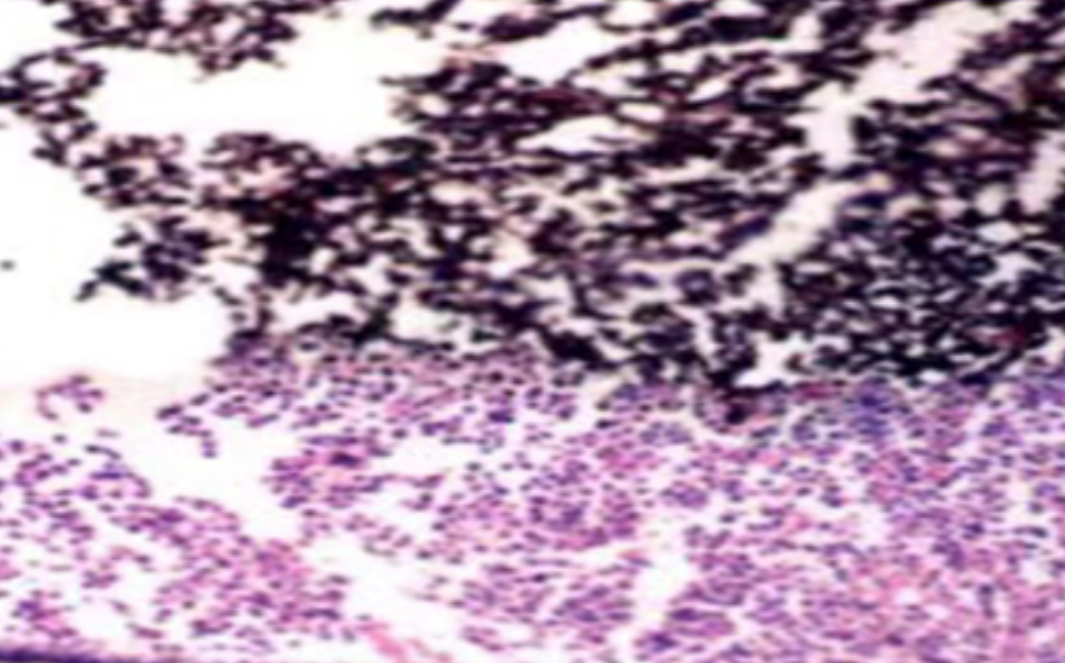

HE染色,全称苏木精-伊红染色法(Hematoxylin and Eosin staining),是最常见的组织切片染色技术之一,用于在显微镜下观察和分析组织或细胞的结构和形态。虽然HE染色是最常见且最基础的染色技术之一,😭但在实验过···

HE染色,全称苏木精-伊红染色法(Hematoxylin and Eosin staining),是最常见的组织切片染色技术之一,用于在显微镜下观察和分析组织或细胞的结构和形态。

虽然HE染色是最常见且最基础的染色技术之一,😭但在实验过程中,很容易出现各种情况导致染色切片质量参差不齐。所以,小编根据以往实验经验,给大家整理归纳出了15个HE染色中的常见问题,还包含问题原因分析以及解决方法哦~

形成原因:切片经梯度乙醇处理后没有完全脱水,导致二甲苯透明、中性树胶封固后残留大量水分。 解决方法:首先移去盖玻片,用二甲苯溶解封固剂如中性树胶,再将切片置入无水乙醇内,待切片重新脱水完全后,用二甲苯透明处理,中性树胶封固。要注意所有用于脱水和透明的液体,在使用一定时间后,应及时更换。 二、细胞核呈红、棕色 形成原因:苏木精染色液过度氧化,切片在苏木精染液染色后返蓝不足。 解决方法:每次染色之前检查苏木精染色液的染色能力,发现苏木精染色液氧化过度应及时更换。此外,切片经苏木精染色后,要给切片以足够的蓝化时间,蓝化过程可用流水、温水、弱碱性溶液(如稀氨水或0.2%碳酸氢钠)等处理。 三、切片在脱蜡后出现大片白色斑点 形成原因:由于烤(烘)片温度太低,切片上的组织蜡膜在脱蜡前没有充分烤(烘)融化。或是因为切片在二甲苯液中停留时间不足,或二甲苯使用过久,造成的脱蜡不彻底。 解决方法:若是由于切片烤(烘)温度低所致,可以先用二甲苯去除切片上的封固胶,然后重新用二甲苯脱去切片上的石蜡,再进行后续染色。若是由于切片在脱蜡的二甲苯中停留时间不足或脱蜡二甲苯使用过久浓度不足所致,则需将切片退回到二甲苯中,停留较长时间,或更换二甲苯液体重新脱蜡,再入乙醇重新脱二甲苯,入0.5%盐酸水溶液褪色后,重新HE染色。 四、细胞核苍白暗淡,即苏木精染色太淡 形成原因:切片在苏木精染色液停留时间太短;苏木精染色液过度氧化,失去染色能力,不能再继续使用;分化步骤处理时间过长;固定不及时。此外值得注意的是,若骨组织细胞核暗淡,大多是脱钙过度造成的。 解决方法:切片重新染色。如果组织在酸性固定液(如Zenker、Bouin)或非中性缓冲甲醛液固定时间过长,细胞核染色能力将减弱,需增加其在苏木精染色液的时间,或用一些方法增加组织的嗜碱性,以改善细胞核的着色。例如,上述组织玻片可以使用Weigert铁苏木精染色液。如果组织是用Zenker液固定的,可将切片脱蜡后放在5%碳酸氢钠溶液3~4h,流水冲洗5min后染色。如果组织是用Bouin液固定的,可将切片脱蜡后放在5%碳酸锂1h,流水冲洗10min后染色。 五、细胞核过染,苏木精染液占据了细胞质 形成原因:玻片在苏木精染色液停留时间过长,或是切片太厚、分化步骤时间太短。 解决方法:如果不是因为切片太厚(用显微镜仔细上下微调,只有一二层细胞核层次),就需将切片进行脱色、漂白、重新染色,适当调整染色和分化时间。但如果确定是由于切片太厚导致的细胞核过染,则需要重新切片。 六、伊红着色淡 形成原因:可能是伊红染液pH值大于5,也可能是蓝化液残留过多,切片太薄,或是切片经伊红染色后在乙醇脱水时间过长。 解决方法:检查伊红染液pH值,必要的话,用乙酸将其调节在4.6~5.0之间,从而使伊红染色色彩艳丽。此外,确保每次蓝化步骤完成后,使用的弱碱性溶液被充分洗去,玻片上没有残留的弱碱性溶液。最后,检查切片的厚度,且脱水时不要让切片在低浓度乙醇中停留时间过长,因为含水多的低浓度乙醇会将切片伊红的颜色分化掉。 七、细胞质过染、分色不足 形成原因:伊红染色液浓度太高,特别是存在焰红燃料、四溴四氯荧光素钠。切片在伊红染色时间过长,或是切片在伊红染色后经乙醇脱水步骤时时间太短,而使乙醇分化伊红的作用不能产生,都能够使细胞质过染。 解决方法:适当稀释伊红染色液,减少伊红染色时间,或使切片在乙醇脱水等步骤时,停留时间相对均匀。同样,也要检查切片的厚度是否合适。 八、切片中出现蓝黑色沉淀物 形成原因:苏木精染色液中的金属膜黏附在玻片上。 解决方法:染色前仔细过滤苏木精染色液,建议使用半氧化苏木精染色液,如Gill苏木精染色液,可以避免过多的金属膜产生。 九、光镜下切片某些区域难以聚焦 形成原因:盖玻片上可能有封固切片的封固剂。 解决方法:移去盖玻片,重新用干净的盖玻片封片。检查切片封片方法,是人工手工封法,还是机器自动封法,如有问题及时调整。 十、封固剂从盖玻片与载玻片之间的缝隙回缩 形成原因:盖玻片弯曲或不平整,或是封固剂含二甲苯过多,稀释过度。 解决方法:移去盖玻片,重新找一张盖玻片,用干净的封固剂封片。如用手工封片法,保证在封固结束时,封固剂容器盖子为紧闭状态。且尽量使用小的容器盛装封固剂,一旦封固剂太黏稠,就可以选择废弃。 十一、细胞核呈灰蓝状态 形成原因:可能由于组织处理温度过高、过热,在液体石蜡中停留的时间过长。或是固定时间太短后,直接在高浓度的乙醇中进行了脱水处理。 解决方法:理论上来说,仅在组织浸蜡步骤才进行加热,组织不能在热蜡液中停留太久。如果由于某些原因不能进行下一步包埋处理,可将组织连同塑料包埋盒一并放置在室温空气中,冷却凝固,以备包埋。待需要包埋时再重新加温直至石蜡融化即可。组织在处理前必须确保固定良好,脱水最好能从低浓度的乙醇开始。 十二、类色素的点状结晶和黑色光滑细胞核 形成原因:这种裸核改变是因为切片封片前放置在空气中的时间太长,以至于二甲苯挥发,切片干燥。 解决方法:移去组织切片上的盖玻片和封固剂,重新处理。将切片水洗数分钟,然后重新脱水、透明、封固。封片过程中要保持组织切片的轻度湿润,尽量不要让其干燥。 十三、染色过淡或过浓 解决方法:如果染色过淡,可以增加染色剂的浓度、延长染色时间或更换新鲜的染色剂;如果染色过浓,则应减少染色剂的浓度或缩短染色时间。 十四、切片出现叠加褶皱 形成原因:新购买的玻片洁净度不够、用镊子撑开切片时操作不够熟练未能平整伸展,或玻片表面有油脂,切片粘贴不牢。另外,烤片时间不足、烤片温度过低或切片过厚造成切片脱落,都会造成重叠或有皱褶的情况。 解决方法:新购买的玻片最好能用硫酸清洁液浸泡一晚,然后流水冲洗干净。在适宜的温度下烤片时间宁长勿短,保证有充足的烤片时间和温度。另外,切片刀要锋利,才能切出厚薄适宜的切片,保证切片不会因为过厚而脱落。 十五、组织残缺不全或有刮划痕迹 形成原因:组织残缺不全是由于切片时修整蜡块时深度不够、组织没有全部暴露于切面。切片的刮划痕迹是由于切片刀的刀锋有缺口、包埋的组织有异物,或是钙化组织、骨组织及包埋石蜡有沙粒造成的。 解决方法:修整蜡块时保证组织块全部暴露于切面,切片时保证切片刀的锋利没刀口。同时在组织取材时去除手术异物和钙化组织。最后,骨组织要完全脱钙,这样可以保证切片的完整和平整美观。 *注:由于实验中导致结果出现误差的原因多种多样,以上内容仅供参考,具体根据实际情况进行判断。